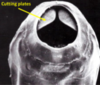

Morphology of bunostomum

A

- Anterior end is bent dorsally

- The buccal capsule is big and bears

- Ont the dorsal margin a dorsal cone

- On the ventral margin margin a pair of cutting plates